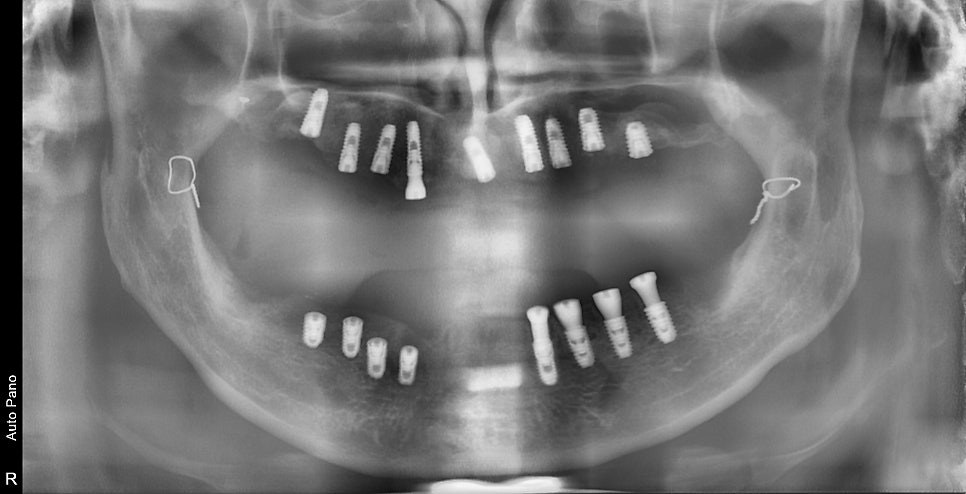

처음 내원해 주셨을 때 엑스레이 사진입니다.

과거에 턱 관련 수술도 받으신 흔적이 보이고

다수의 치아가 빠진 상태로 오랜 시간이 지나셨으며,

기존 치아들 주변도 치주염에 의해 동요도가 발생되었고 발치가 불가피해 보였습니다.

위턱뼈같은경우 치아가 상실된 기간이 길어 노란색으로 표시된 부위의 잔존뼈의 양이 너무 작았습니다.

수술을 위해서는 상악동 거상술이라고 하는 상악동 부위에 뼈를 만들는 수술이 필요해 보였습니다.